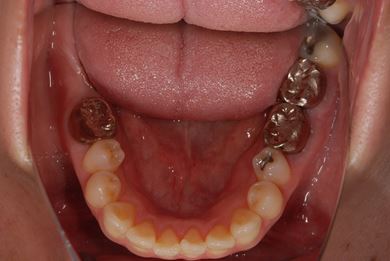

| 性別/年齢 | 女性 / 39歳 | ||||||||||||||||||||||||||||||||

| 主訴 | 右奥歯の虫歯と、右奥のインプラント治療について相談。 | ||||||||||||||||||||||||||||||||

| 治療方針 | 右下奥欠損部分をインプラント治療にて、機能的・審美的回復を行う。 | ||||||||||||||||||||||||||||||||

| 治療内容 | インプラント1本、ハイブリッドセラミッククラウン1本 | ||||||||||||||||||||||||||||||||